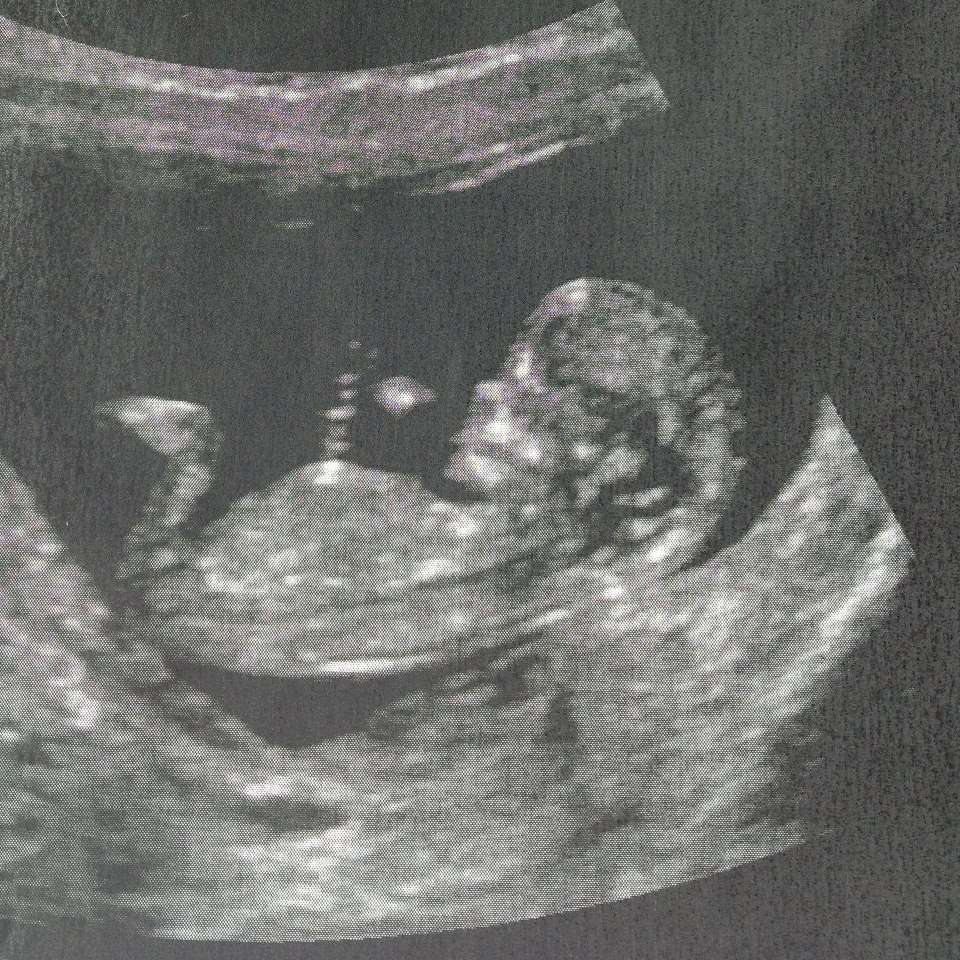

Not finding out the gender until baby is born in a few months and would love some predictions!

Skull predictions only for fun; but that is a classic boy skull.

Boy skull, but the skull theory is to be taken with a grain of salt.